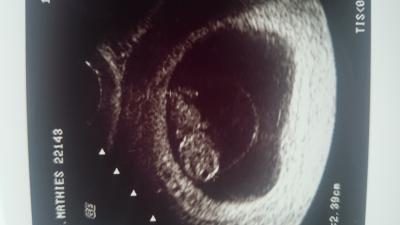

Mal wieder ein neues Foto von unserem Krümel, er ist nun 2,4 cm groß und bewegt sich fleißig. Mit den Händen hat er die ganze Zeit im Gesicht herum gespielt . Der FA konnte den Magen und die Blase sehen und ich habe den Herzschlag gehört, es war soooo toll.

Und ein wahnsinnig schönes Bild hast du :) schon ein richtiges baby ;) ich hatte letzte Woche noch ne Bohne von 1,3 cm und kann gar nicht abwarten das die nächsten 3 Wochen schnell umgehen ... ;)